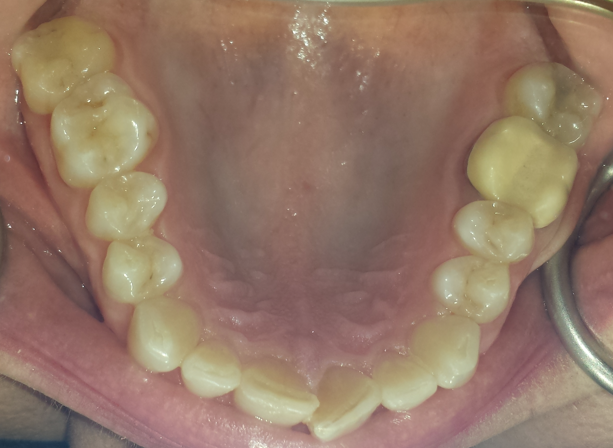

Initial cone beam computed tomography (CBCT) revealed low tongue posture (Figure 1). Figures 2, 3, and 4 show the frontal, maxillary occlusal, and mandibular occlusal views of the dentition, respectively. Clinical examination identified a scalloped tongue with low muscle tone and difficulty achieving palatal suction. Dental findings included upper and lower arch crowding, advanced tooth wear consistent with attrition, a deep skeletal bite evident on cephalometric analysis, and a marked loss of vertical dimension of occlusion (VDO) (Figures 5 and 6).

Figure 4.

(more ...)